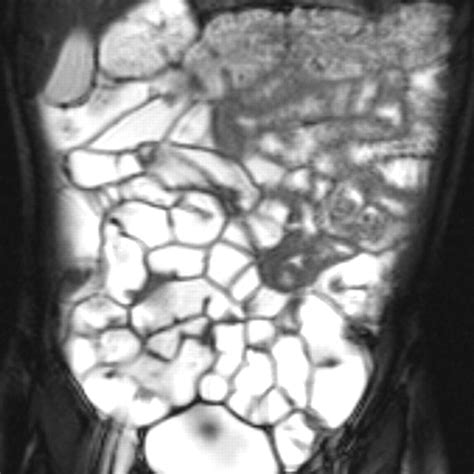

The Small Bowel Follow Through (SBFT) is a radiological examination that uses X-rays to visualize the small intestine. This procedure is particularly useful for detecting abnormalities such as strictures, obstructions, tumors, and inflammatory conditions like Crohn’s disease. The SBFT involves ingesting a barium solution, which coats the lining of the small intestine, making it visible on X-ray images.

• X-ray Imaging: As the barium solution moves through the small intestine, a series of X-ray images are taken at regular intervals. This allows the radiologist to observe the movement of the barium and identify any abnormalities.

• MRI Enterography: Similar to CT enterography, but uses magnetic resonance imaging instead of X-rays.